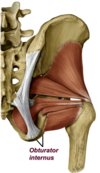

Obturator internus

- obturator foramne, membrane on medial side–> out through foramen, 90 degree angle–> out lesser sciatic–> greater trochanter

- N. to obturator internus (L5, S1, S2)

- same nerve roots and inferior gluteal nerve

- External thigh rotation

deep gluteal muscle